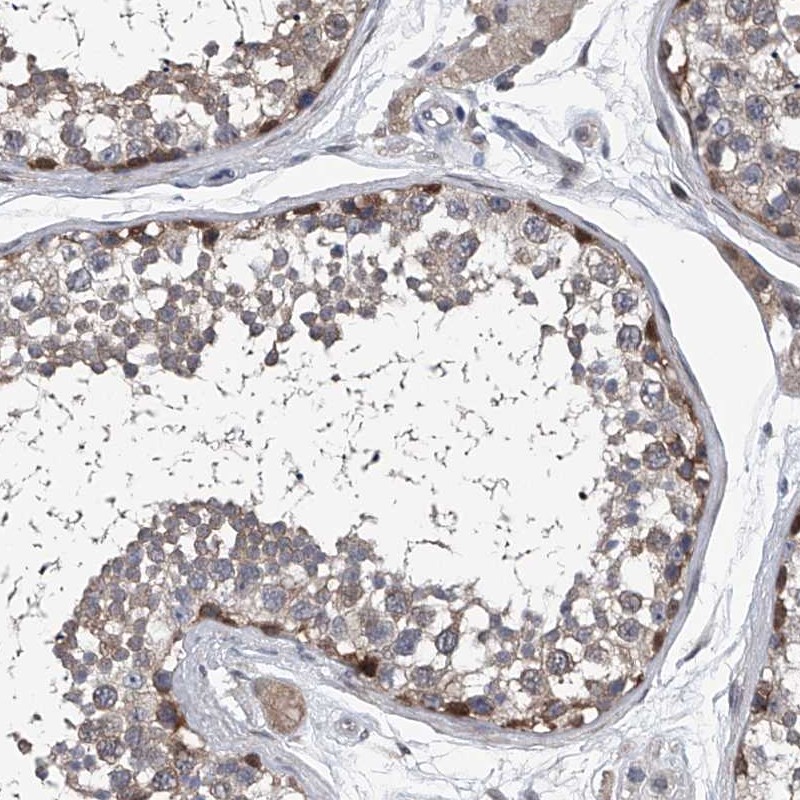

Immunohistochemical staining of human testis shows strong cytoplasmic positivity in cells in seminiferous ducts.